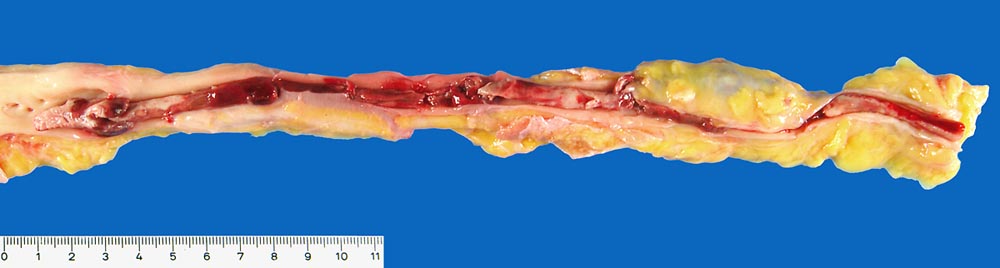

Tiefe Beinvenenthrombose

Nicht ganz frischer wandadhärenter, okklusiver zusammengesetzter Thrombus der rechten Vena femoralis, bis in die Vena poplitea reichend.

Nicht ganz frische parazentrale Lungenembolie des rechten Lungenoberlappens. Multiple ältere und nicht ganz frische periphere Lungenembolien beidseits. Ausgedehnter nicht ganz frischer hämorrhagischer Lungeninfarkt

Polycythaemia vera